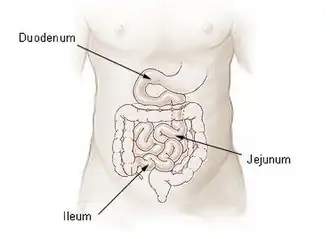

The jejunum is the second part of the small intestine in humans and most higher vertebrates, including mammals, reptiles, and birds. Its lining is specialized for the absorption by enterocytes of small nutrient molecules which have been previously digested by enzymes in the duodenum.

The jejunum lies between the duodenum and the ileum and is considered to start at the suspensory muscle of the duodenum, a location called the duodenojejunal flexure.[4] The division between the jejunum and ileum is not anatomically distinct.[5] In adult humans, the small intestine is usually 6–7 m (20–23 ft) long (post mortem), about two-fifths of which (about 2.5 m (8.2 ft)) is the jejunum.[4]